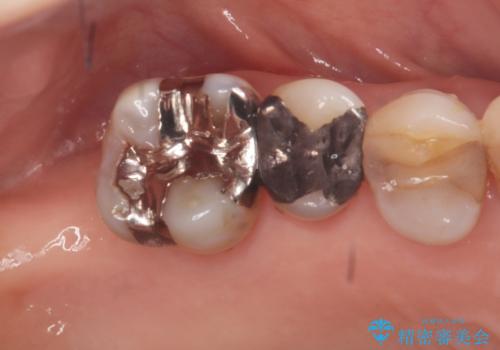

- 右上の奥歯(6番)が重度の歯周病により保存困難な状態であること、およびその後ろの7番もすでに失われていることを主訴にご来院されました。このままでは咬み合わせの機能が大きく低下してしまうため、抜歯後の早期回復と長期安定性を考慮し、インプラント治療を提案しました。治療計画は、

6番を抜歯すると同時にインプラントを埋入する抜歯即時埋入

失われた7番の部分にも同時にインプラントを埋入 の2本同時のインプラント埋入により、治療期間を短縮し、奥歯全体の機能再建を目指しました。

今回の治療では、まず重度歯周病の右上6番を慎重に抜歯し、その直後に6番と、すでに欠損していた7番の部分に、合わせて2本のインプラントを埋入しました。